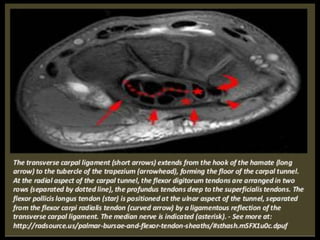

Elbow Joint.

Indication.

-Pain.

-Swelling.

-Stiffness.

-Deformity.

-Instability.

-Paraesthesias.